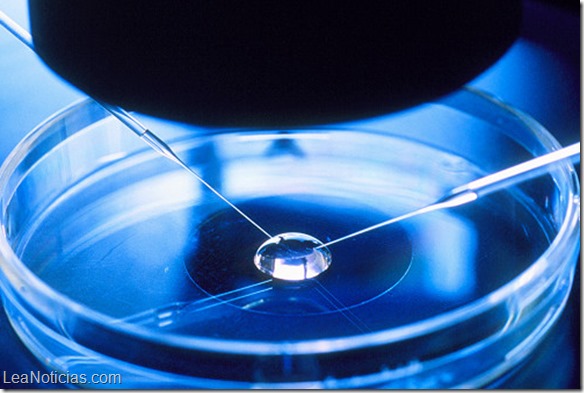

Uno de los mayores obstáculos es el costo de los complejos y sofisticados laboratorios donde la fertilización «in vitro» del óvulo tiene lugar.

Las mejores condiciones para que un espermatozoide fertilice un óvulo fuera del cuerpo son ligeramente alcalinas, a una temperatura de 37ºC.

Normalmente, esto requiere un sofisticado laboratorio equipado con enormes ventiladores, incubadoras complejas y un suministro de gases costosos.

Para los seres humanos la técnica tuvo que ser refinada para crear un sistema cerrado y por lo tanto minimizar cualquier riesgo de contaminación.

Cantidades precisas de ácido cítrico y bicarbonato de sodio se mezclan en un tubo de ensayo. Las burbujas de CO2 que esto crea son alimentadas a través de un tubo en un segundo tubo de ensayo que contiene un medio de cultivo para el embrión.

Una vez que la atmósfera se estabiliza, el óvulo y el esperma se inyectan en el tubo de ensayo que contiene el medio de cultivo.

Al día siguiente, este tubo de ensayo pasa por un microscopio para ver si contiene un embrión, lo que significa que la fertilización del óvulo tuvo lugar.

Si se crea un embrión de forma exitosa, se transfiere desde el tubo de ensayo hasta el útero de la mujer después de unos seis días.